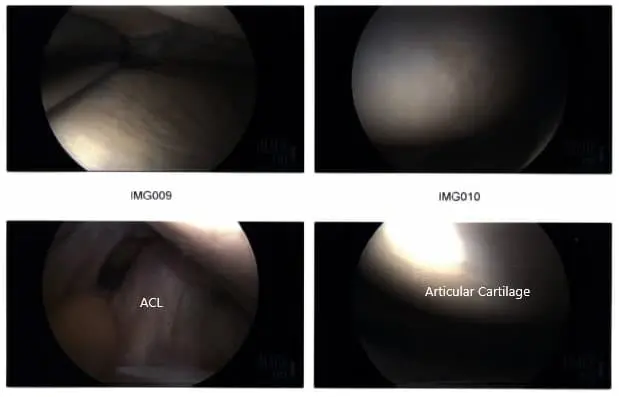

Intraoperative arthroscopic images.